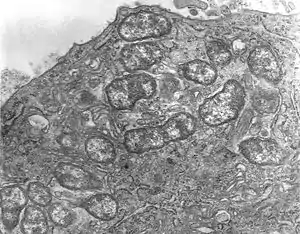

Orientia tsutsugamushi is a Gram-negative bacterium and is a permanent (obligate) parasite in mites. Within a single host cell, O. tsutsugamushi rapidly divides into many individuals as shown in Figure 1. A unicellular organism, it is oval shaped and measures 0.5 to 0.8 µm wide and 1.2 to 3.0 µm long. Due to similarity, it was previously classified in the genus Rickettsia among other bacteria, but later assigned a separate genus, Orientia,[20] which it shares (as of 2010) only with Candidatus Orientia chuto.[21] It is broader but shorter than other rickettsial bacteria, which are rod shaped and on average measure 0.25 to 0.3 µm wide and 0.8 to 1 µm long.[22] During reproduction, it divides (by binary fission) into two daughter cells by the process of budding. While undergoing budding, it accumulates on the host cell surface, unlike other bacteria. One complete budding cycle takes 9 to 18 hours.[23]

The structure of O. tsutsugamushi (revealed by transmission electron microscopy) is shown in Figure 2. The bacterium is enclosed by a cell wall on the outside and cell membrane on the inside. The cell covering takes up stains such as Giemsa and Gimenez stains. Although its cell wall has a classic bacterial double layer, its outer leaflet is much thicker than the inner one, which is just the opposite in Rickettsia species.[24] A capsule layer that forms a spherical halo in other bacteria is missing. The cell wall is less rigid due to the absence of peptidoglycan, which is otherwise characteristic of the rigid cell walls of other bacteria. Classic bacterial lipophosphoglycans such as muramic acid, glucosamine, hydroxy fatty acids, heptose, and 2-keto-3-deoxyoctonic acid are also absent in the cell wall. Due to the absence of peptidoglycan, the bacterium is naturally resistant to all β-lactam antibiotics (such as penicillin), to which Rickettsia species are normally sensitive to.[25] Its genome totally lacks the genes for lipophosphoglycan synthesis, but does contain some for those of peptidoglycan. Important genes essential for peptidoglycan systhesis such as alr, dapF and PBP1 are missing: alr encodes an enzyme L-alanine racemase, which converts L-alanine to D-alanine in the first step of peptidoglycan synthesis pathway; dapF encodes diaminopimelate epimerase, which convert LL-2,6-diaminoheptanedioate (L,L-DAP) to meso-diaminoheptanedioate (meso-DAP); and PBP1 encodes penicillin-binding protein-1 (PBP1), which converts periplasmic lipid II to peptidoglycan. Thus, the bacterium cannot synthesise a typical peptidoglycan cell wall, and instead makes a peptidoglycan-like structure on its surface.[26] The cell membrane is also chemically different in its protein composition, and this difference gives rise to strain variations within the species itself.[27] The cytoplasm is clear and shows distinct DNA and ribosomes.